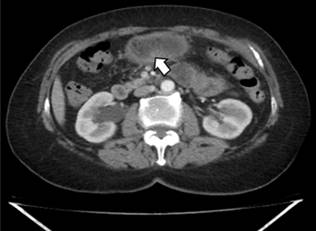

Se realizó una segunda endoscopia digestiva alta para definir la localización de la masa y la toma de biopsias; se observó un engrosamiento grave de la mucosa de curvatura mayor con gran eritema. Se tomaron múltiples biopsias y, de forma sorpresiva, se extrajo una espina de pescado de 3,5 cm (Figuras 2 y 3). Posteriormente, se inició el manejo antibiótico para absceso gástrico; se interrogó nuevamente a la paciente, quien negó el consumo de pescado en el último mes o meses previos; se realizó un seguimiento con una TAC abdominal, en la que se evidenció una disminución del tamaño de la lesión y escaso líquido que no amerita drenaje (Figura 4). Se completó el tratamiento antibiótico y se realizó una ecografía de abdomen de control con el absceso resuelto.